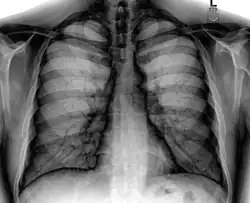

Placa posteroanterior de tórax en el sujeto normal. -

Placa lateral de tórax en el sujeto normal. El lado izquierdo del tórax se apoya sobre el cassette de la película radiográfica para impedir la magnificación del corazón. Las placas posteroanterior y lateral constituyen el "par radiográfico de tórax". -